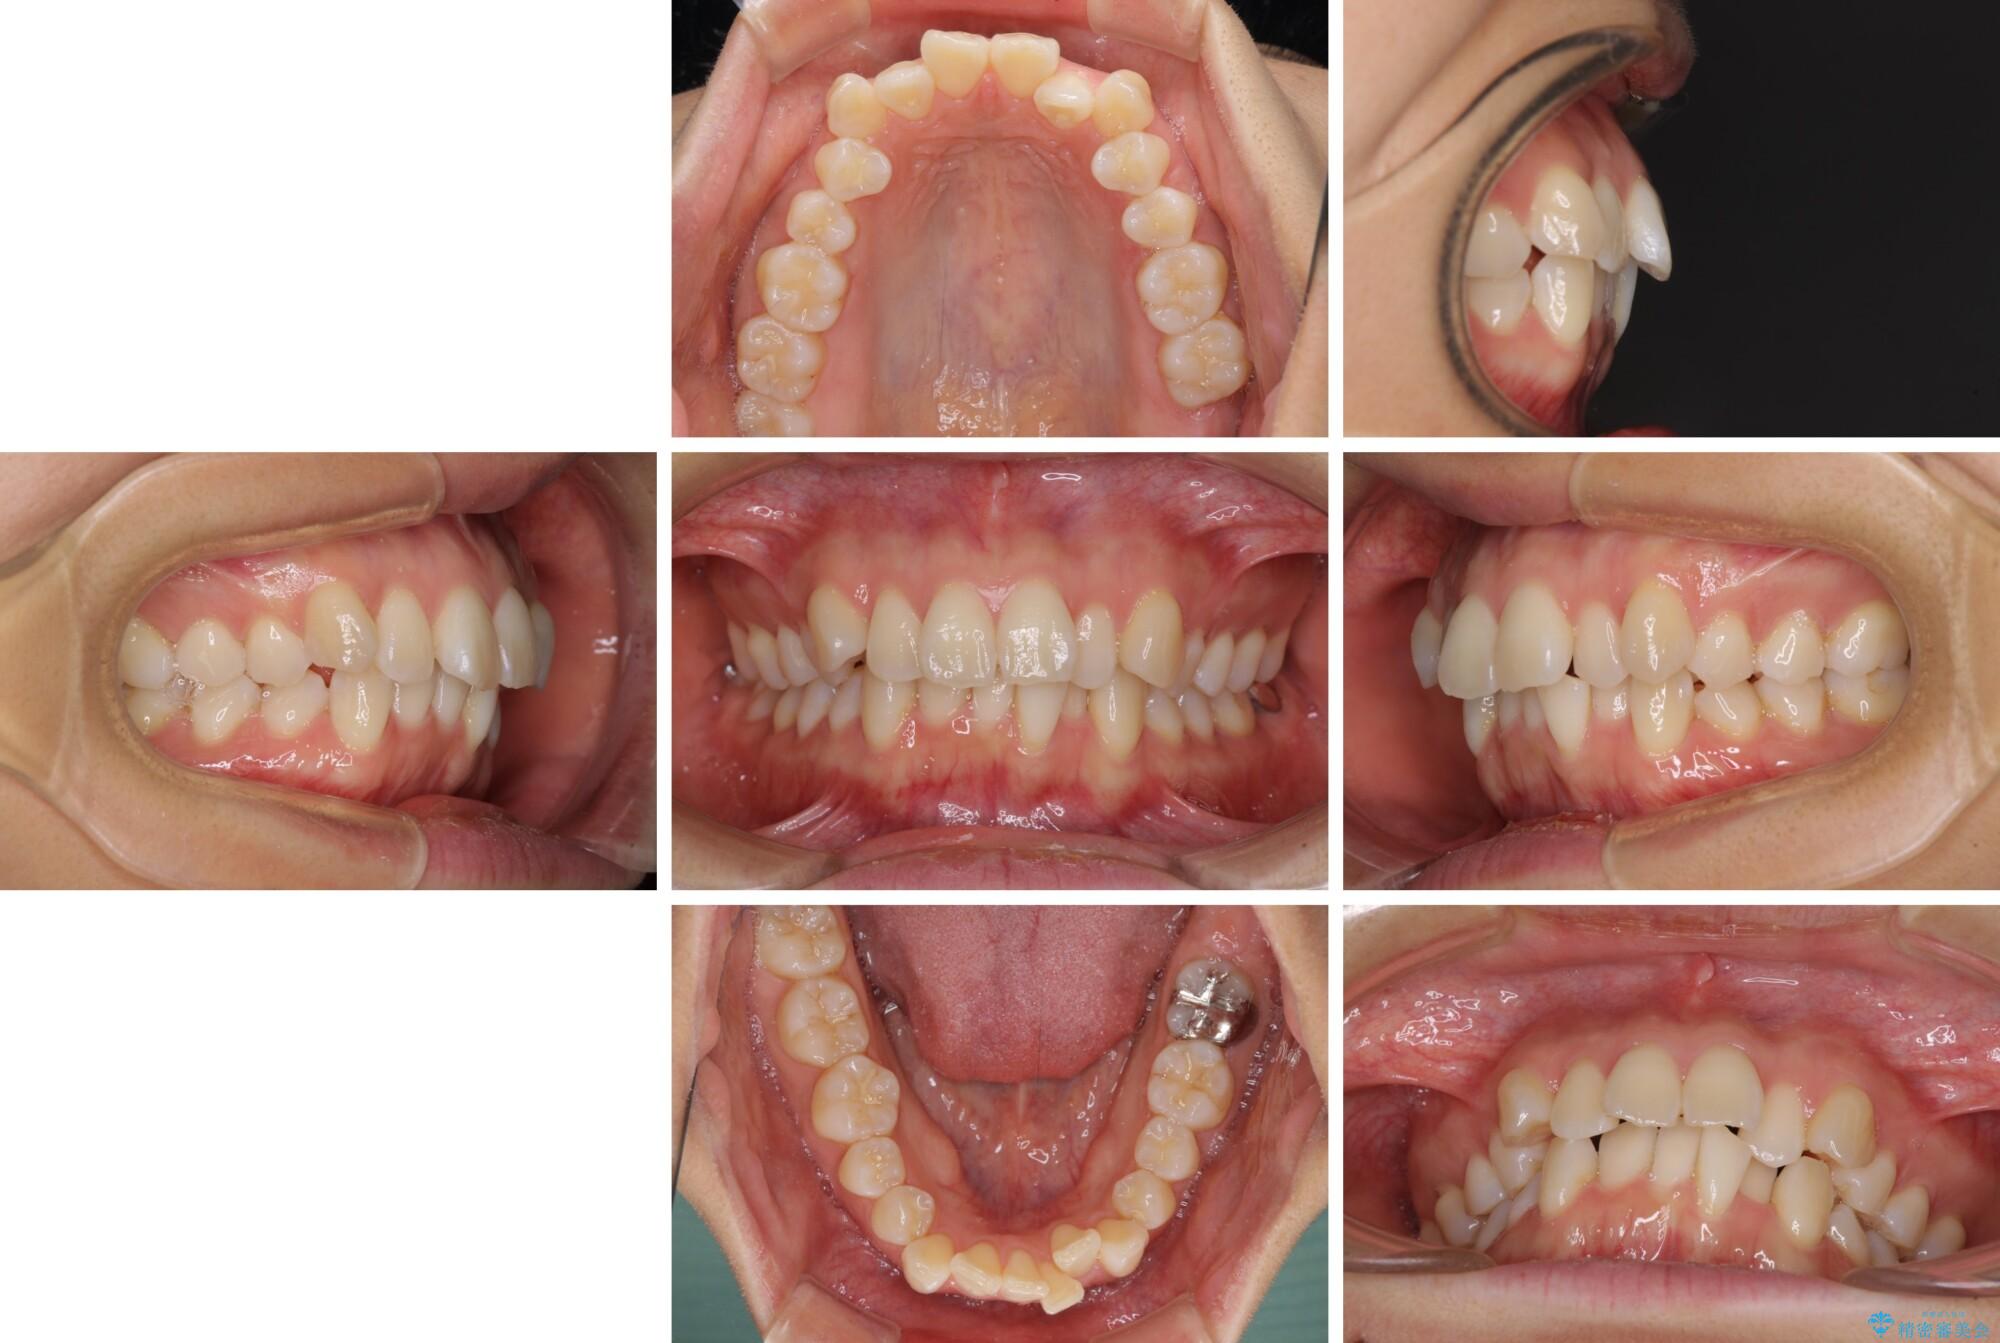

前歯のデコボコを抜歯矯正で改善 メタル装置で費用を抑えるの症例写真前歯のデコボコを抜歯矯正で改善 メタル装置で費用を抑える